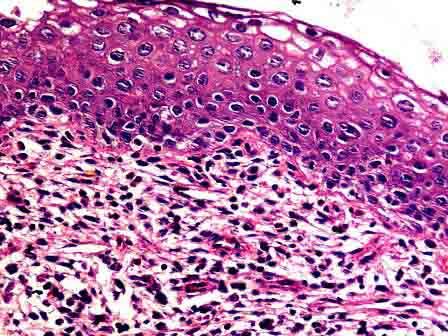

问题 女性,34岁,接触性出血一年余加重一周,行子宫切除,显微镜下见鳞状上皮细胞具异型性,异型细胞超过上皮全层2/3,但不及3/3。如图,应诊断为 ( )

选项 A.CINⅠ级 B.CINⅡ级 C.CINⅢ级 D.原位癌 E.浸润癌

答案 C